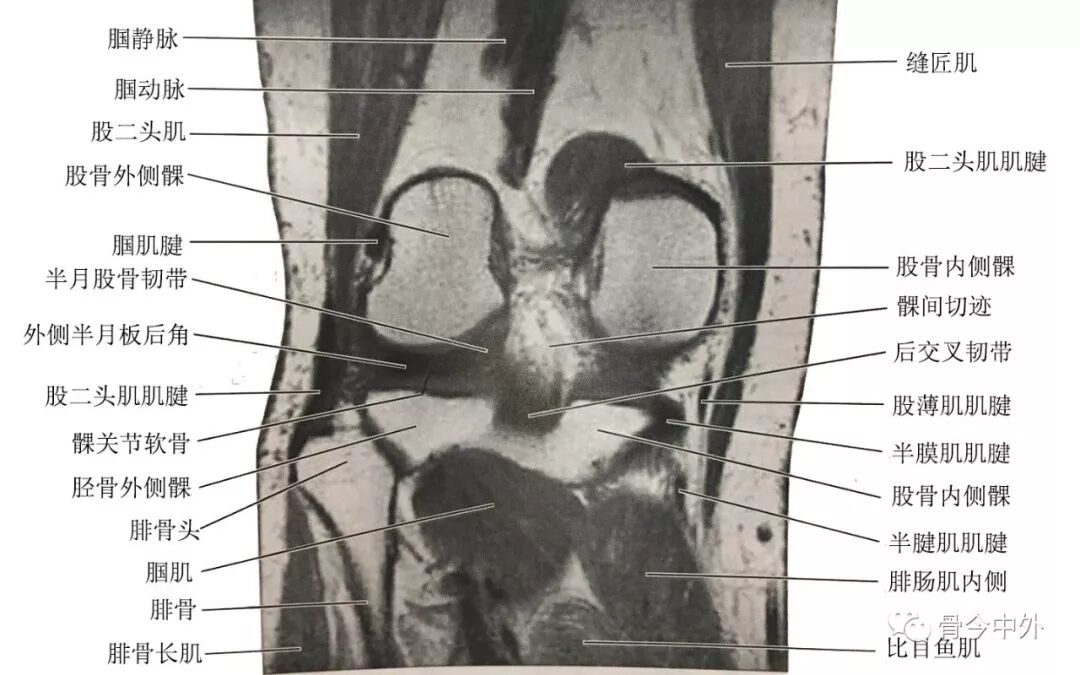

(2)膝中部冠状断层:该层面解剖关系结构如图

膝中部冠状断层

(3)膝后部冠状断层:该层面解剖关系结构如图

膝后部冠状断层